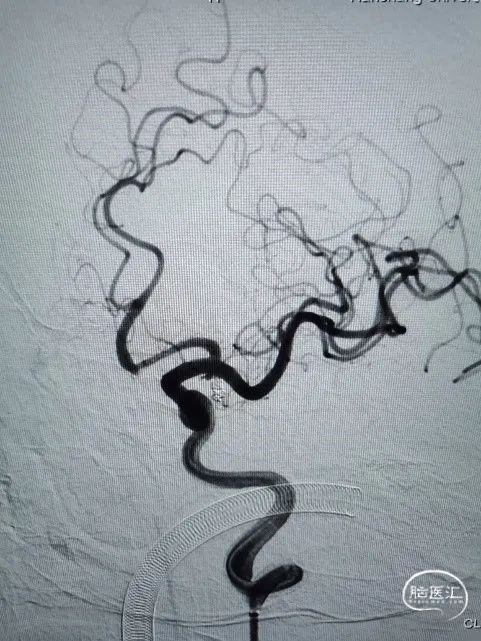

术后即刻造影

动脉瘤栓塞满意,Raymond分级I级。左侧颈内动脉正侧位造影提示血管显影良好,未见血管痉挛等。